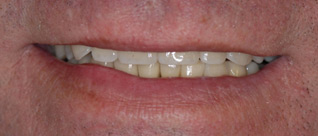

Je veux retrouver l’ensemble de mes dents individuelles comme «au naturel».

Solution : autant de couronnes fixes sur implants que de dents manquantes.

Je veux supprimer les bridges et retrouver un beau sourire.

Au final toutes les dents sont individualisées et les manquantes remplacées par des implants.